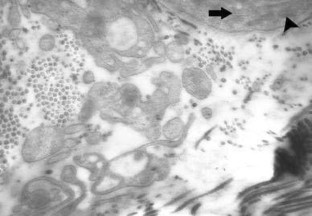

Thymoquinone (TQ) is a plant extract that has been shown to have antioxidant, anti-inflammatory, angiogenic, antimicrobial, and anticarcinogenic effects. The aim of this study is to research how the use of TQ affects flap viability. 42 rats were placed into 6 groups, with 7 rats in each. A 3 × 10 cm McFarlane flap model was used on the test animals. The sham group had used neither surgical nor TQ treatment. The control group had surgery but no treatment afterwards. The preoperative TQ group was given oral doses of 2 mg/kg. TQ for 10 days preoperatively with no treatment after the surgical procedure. The postoperative TQ group received oral doses of 2 mg/kg TQ for 10 days after the surgical process. The preoperative + postoperative (pre + postoperative) TQ group was given oral doses of 2 mg/kg TQ for 10 days both preoperatively and postoperatively. Finally, the dimethylsulfoxide group received 10 mg/kg dimethylsulfoxide (DMSO) for 10 days both preoperatively and postoperatively. Ten days after surgery the findings were evaluated. The average rates of necrosis were found to be 29.7 % in the control group, 19.18 % in the preoperative TQ group, 13.05 % in the postoperative TQ group, 8.42 % in the pre + postoperative TQ group, and 29.03 % in the DMSO group. The experimental groups had better area measurement, histopathological, and electron microscopic results than the control group (All; p < 0.05). We believe that, because of its antioxidant, anti-inflammatory, and angiogenic properties, thymoquinone is an agent that can prevent ischemia–reperfusion damage and, therefore, prevent necrosis.